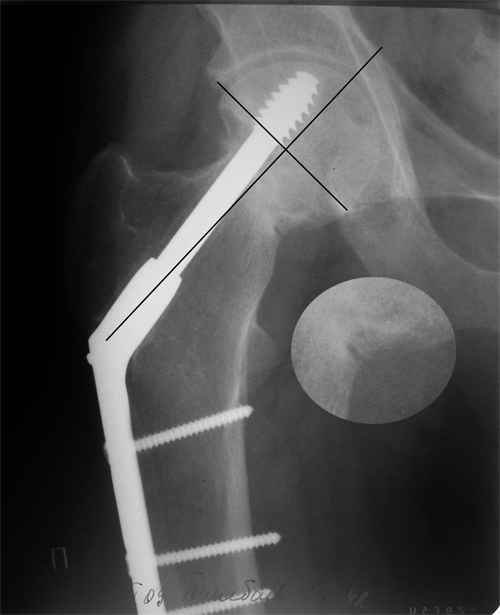

Результат - Псевдоартроз шейки правого бедра (имеются косвенные

признаки разрушения спонгиозной части головки бедра)Планируется -

Работоспособный возраст (43 года).Наиболее приемлемым и реальным

методом лечения предполагается: Удаление конструкций из бедра.

Заполнение полости от винта монолитным аутотрансплантатом из крыла

(крылев) подвздошной кости. Медиализация большого вертела.

Предполагаемый период нетрудоспособности 3-4 мес.